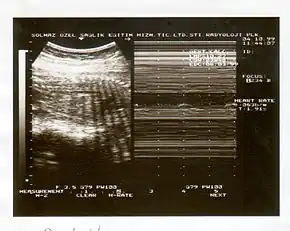

A biophysical profile (BPP) is a prenatal ultrasound evaluation of fetal well-being involving a scoring system,[1] with the score being termed Manning's score.[2] It is often done when a non-stress test (NST) is non reactive, or for other obstetrical indications.

The BPP has five components: four ultrasound (US) assessments and an NST. The NST evaluates fetal heart rate and response to fetal movement. The five discrete biophysical variables are: